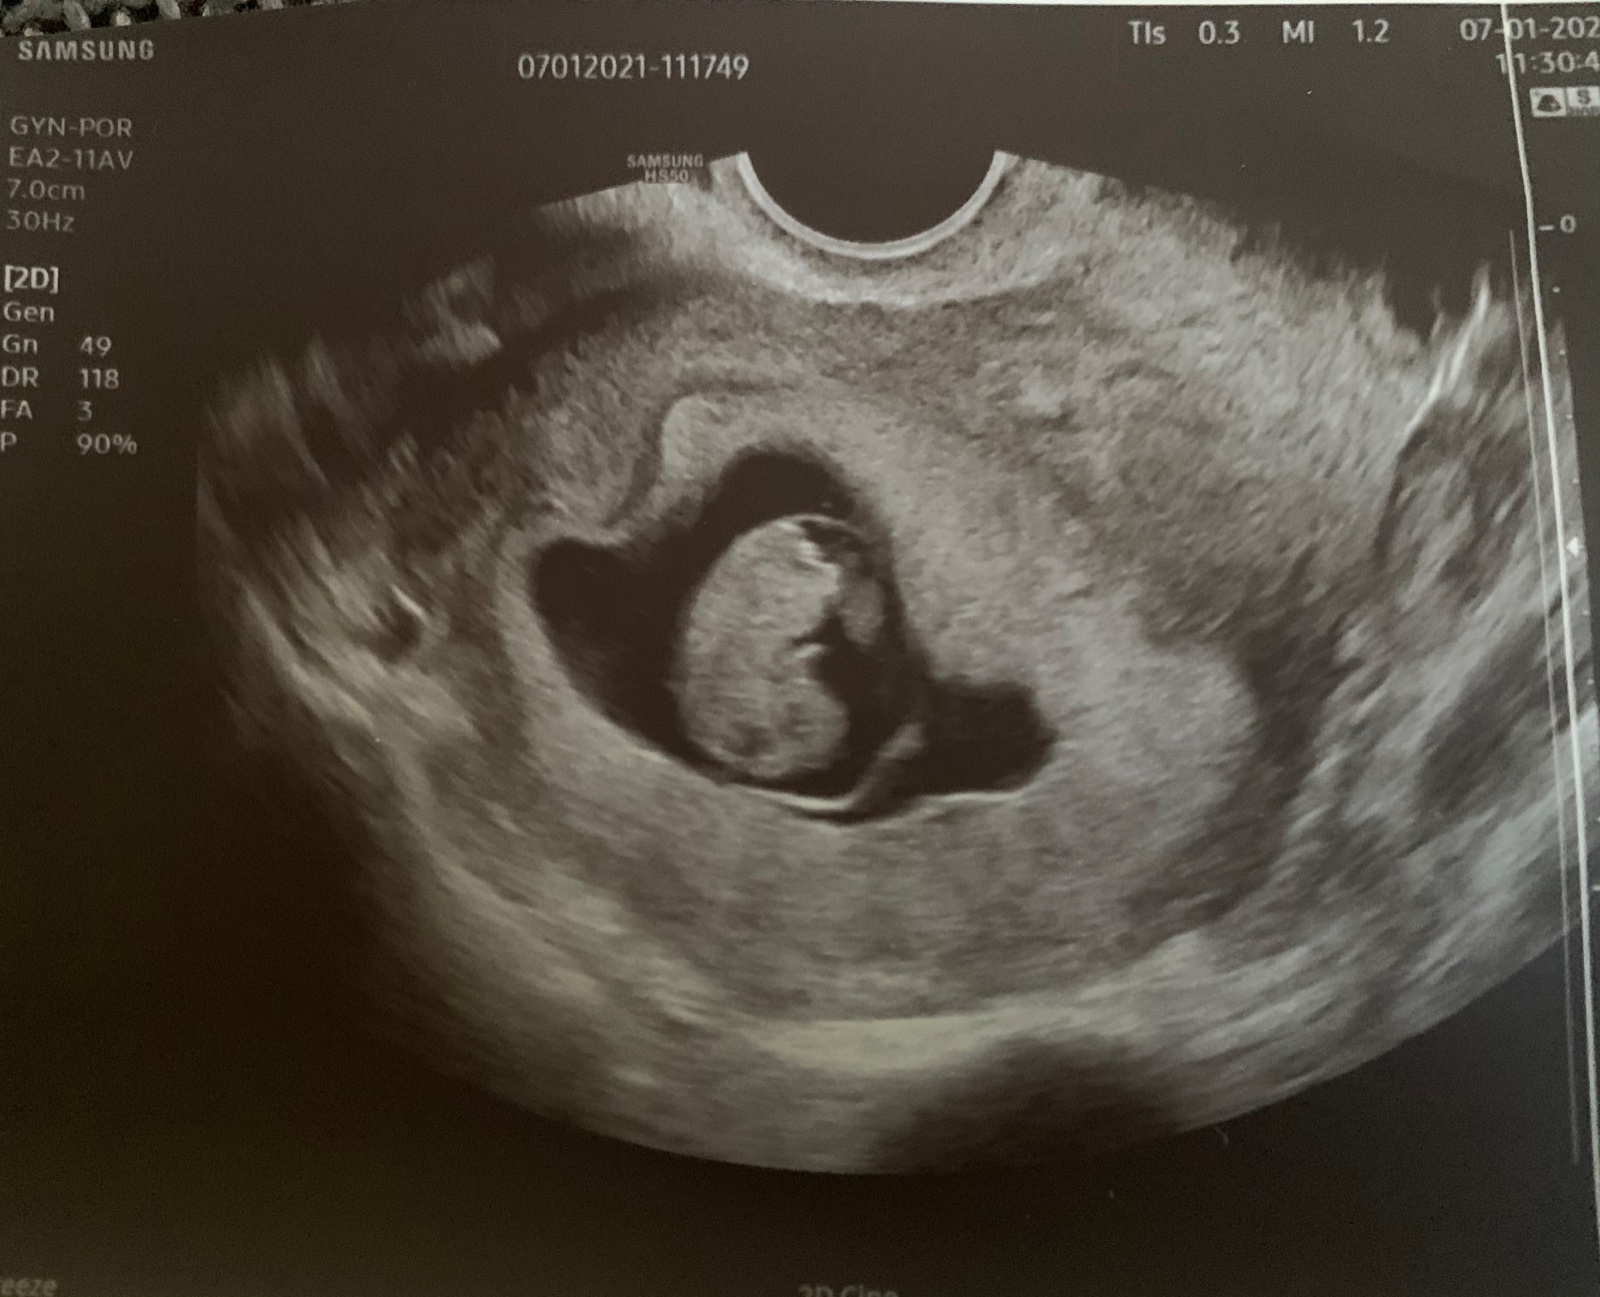

Já dnes u dr dobrý. Už zaznamenala srdíčko, ale jsme prej malinký, ale HCG vysoký. Mám zase kontrolu příští týden.

Hlásím info z kontroly. Vše je v pořádku 🙏. Podle MS 8+4 a podle UZ 9+0, takže u mě musela být ovulace už 11DC. Ještě mě čeká kontrola příští týden, protože jsem se rozhodla změnit gynekolozku.

@miskatus navíc ještě teď v době covidu nesmí být v čekárně tolik lidí, tak se stojí fronta na chodbě a není schopna přijít včas a urychlit to. Ale fotka se jí povedla 😊

@hellblau13 to je nádhera ♥️♥️♥️ Tak ti závidím a zároveň přeji 🙂 zaslouzis si štěstí po tom všem. Tak teď už nebudeš mít takový stres a začneš si konečně užívat 🙂

@hellblau13 To je nadherne miminko moc gratuluji💗🥰